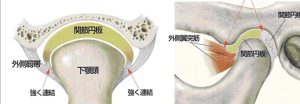

顎の病気で最も多いのは関節内にある関節円板と言うクッションが前方にずれることで起きるカクンカクン言う音が出る状態があります。

顎関節の内部には関節円板があり、これが軸と軸受けとの間にあります。下顎頭は口を開けるときに前方に移動します。その時関節円板は一緒に移動して仮の軸受となります。